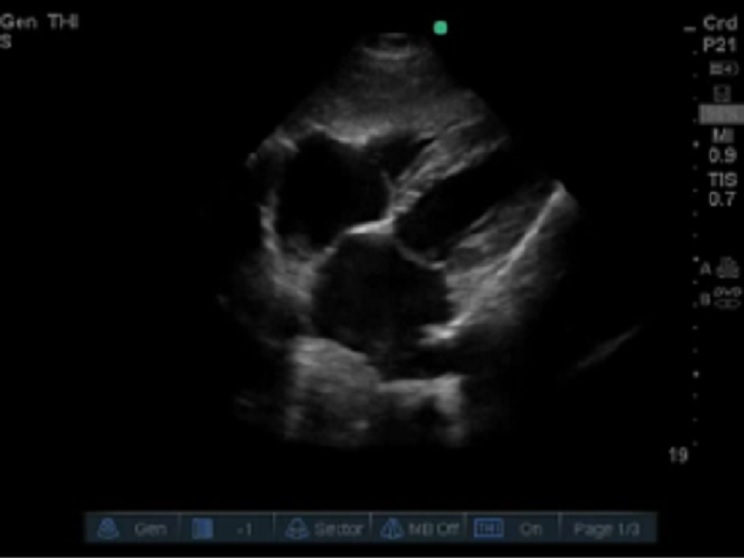

RUSH 右心劳损剑突下视图图像